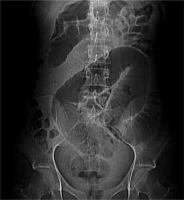

The abdominal ultrasound examination revealed gas bubbles in the portal vein trunk and distended stomach filled with fluid content. The gallbladder and common bile duct were invisible due to compression. Intestinal loops along the entire abdominal cavity were widened up to a maximum of 42 mm and were filled with fluid content. Peristalsis was intensified. Ultrasound revealed a gastrointestinal obstruction. Electrolyte disturbances detected in laboratory tests were corrected by obtaining normalization of urea and creatinine parameters. The computed tomography (CT) showed an obstruction of the jejunum and proximal ileum loops with oedema of the ileum wall up to 12 mm. In the ileum of small pelvis, compact masses with dimensions of 7 cm and 5 cm were observed, with zero contrast enhancement suggesting bezoars (Figure 3).

Proximal obstruction of the small intestine was marked from these masses. Gastroscopy showed oesophageal abnormality along its entire length, it was congested and wallpapered with food residue. An abundant, green mucous lake was exposed in the stomach. Gastric mucosa was hyperaemic. On the upper wall of the duodenal bulb there was a large ulcer about 3 cm in diameter. The ileotomy with evacuation of two trichobezoars with a diameter of about 5 and 7 cm was performed.